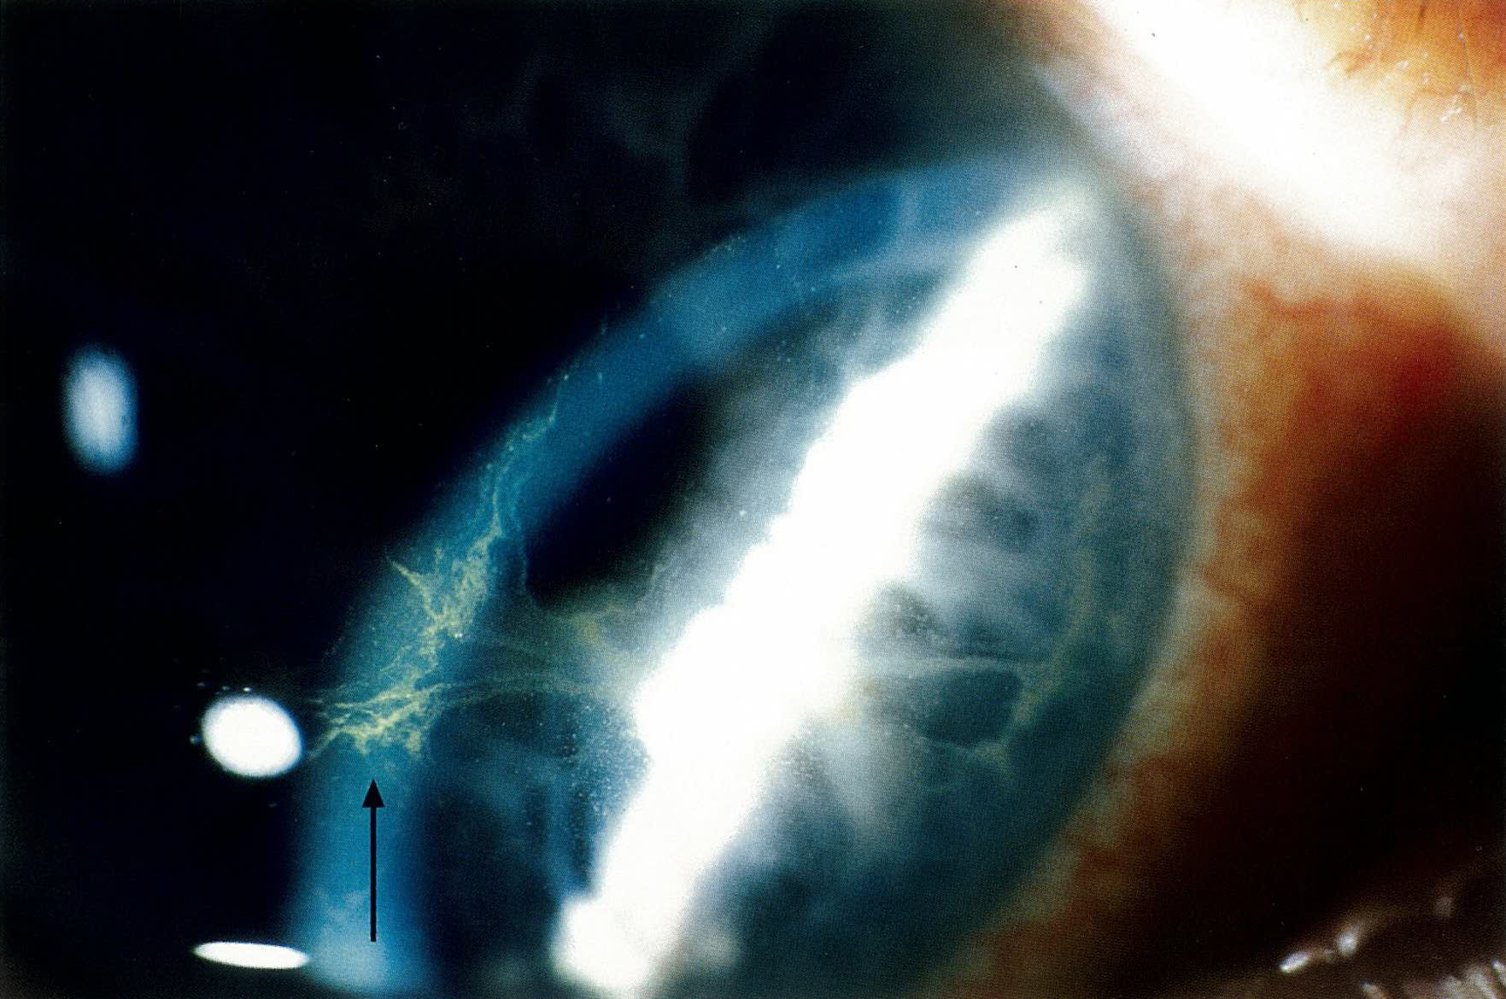

Ocular

• Corneal micro-deposits

• Corneal micro-deposits occur in > 90% of patients and rarely cause symptoms but have the potential to result in halo vision (especially at night), photophobia, and blurred vision. [3]